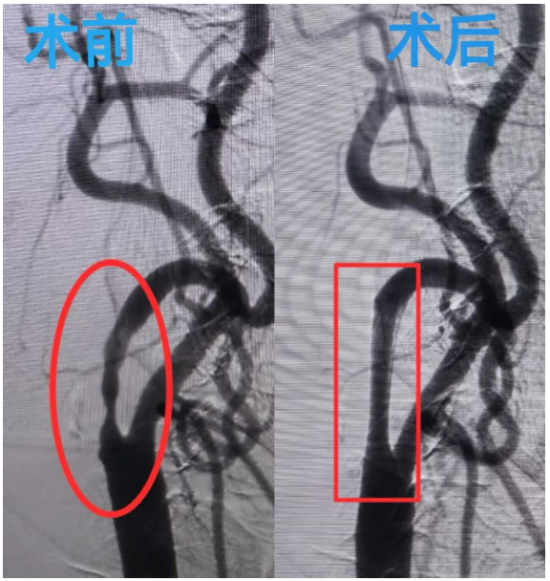

患者抵达总院后,神经内一科医护人员早已做好接诊准备。凭借前期传输的完整病历资料,快速制定诊疗方案。次日,由哈尔滨市第二医院特聘专家李瑞岩教授,神经内一科刘照寒主任,赵越医生组成的神经介入团队为其进行了颈内动脉支架植入手术。手术顺利完成,患者状态良好,不适感消失,术后2天顺利出院。